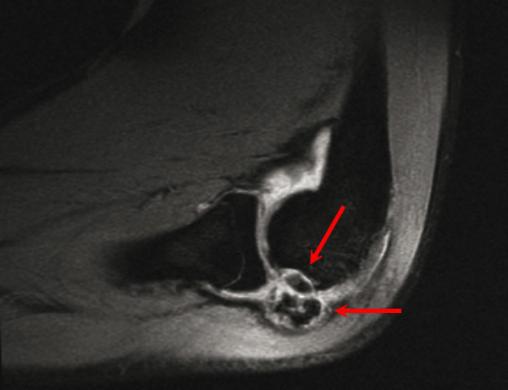

Ostéochondrose articulaire du coude associant un fragment du condyle latéral en place, ainsi que des corps étrangers dans la synoviale articulaire. Voir : P. Journeau, E. Polirzstok, F. Launay, D. Barbier. Lésions osseuses de sollicitation excessive chez l’enfant sportif. Rev Prat 2015;65(8);1084-90.